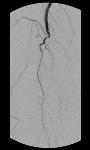

Při vyšetření nemocného se diagnosa stanovuje na základě všech dostupných anamnestických údajů a ze základního vyšetření pohledem a pohmatem. Při odůvodněném podezření na tuto chorobu se provádí nejprve vyšetření tepen ultrazvukem. Toto většinou stačí k vytvoření dobrého diagnostického základu k započetí therapie. U nemocných, kteří nemají noční bolesti a klaudikační interval je delší než 200 metrů, se má zahájit konservativní léčba. Tato spočívá v úpravě životosprávy, v ukončení kouření, v aplikaci léků a vhodném svalovém cvičení. Kontrastní vyšetření tepen rentgenem t.z. angiografie se provádí většinou až v případě, kdy se plánuje operační řešení uzávěrové choroby. To připadá v úvahu u nemocných s krátkým klaudikačním intervalem, nočními bolestmi nebo počínající periferní odúmrtí.

Na základě rtg obrazu tepen lze naplánovat rekonstrukční operaci. Principem těchto operací je v menším procentu případů přímý zákrok na tepně v místě zúžení či uzávěru, kdy se tepna otevře v potřebném rozsahu a uzávěr se odstraní za kontroly zraku. Druhý, více užívaný způsob rekonstrukce, je tzv. by pass, tedy vytvoření náhradního řečiště pomocí vlastní odebrané žíly nebo pomocí umělé protézy. Podmínkou všech rekonstrukčních výkonů je dobrý výtokový trakt, což znamená, že tepny, kam krev přivádíme, jsou dostatečně průchodné, aby se zajistil potřebný proud v novém řečišti. Zejména umělé protézy jsou velmi náchylné k uzávěru při průtoku pod 100-120 ml/min.